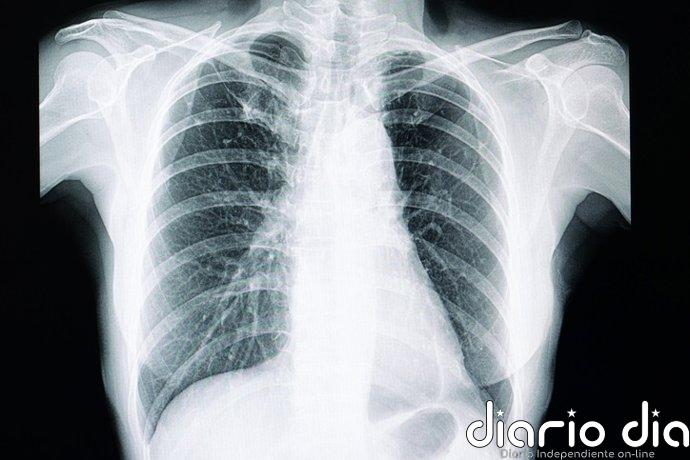

Ni radiólogos ni IA distinguen estas radiografías ‘deepfake’: un estudio alerta de un nuevo riesgo para la sanidad

Ni los radiólogos ni los modelos de lenguaje multimodales (LLM, por sus siglas en inglés) pueden distinguir fácilmente las imágenes de rayos X ‘deepfake’ generadas por inteligencia artificial (IA) de las auténticas, según un estudio de la Escuela de Medicina Icahn en Mount Sinai (Estados Unidos).

Cabe recordar que el término «deepfake» se refiere a un vídeo, fotografía, imagen o grabación de audio que parece real, pero que ha sido creado o manipulado mediante inteligencia artificial. «Nuestro estudio demuestra que estas radiografías deepfake son lo suficientemente realistas como para engañar a los radiólogos, los especialistas en imágenes médicas más capacitados, incluso cuando sabían que se trataba de imágenes generadas por IA», comenta el autor principal del estudio, el doctor Mickael Tordjman, investigador postdoctoral de la Escuela de Medicina Icahn en Mount Sinai.

El primer conjunto de datos incluía imágenes reales y generadas por ChatGPT de múltiples regiones anatómicas. El segundo conjunto de datos incluía imágenes de rayos X de tórax: la mitad auténticas y la otra mitad creadas por RoentGen, un modelo de difusión de IA generativa de código abierto desarrollado por investigadores de Stanford Medicine (Estados Unidos).

«Las imágenes médicas generadas mediante deepfake suelen parecer demasiado perfectas», detalla Tordjman. «Los huesos son excesivamente lisos, las columnas vertebrales anormalmente rectas, los pulmones excesivamente simétricos, los patrones de los vasos sanguíneos excesivamente uniformes y las fracturas aparecen inusualmente limpias y consistentes, a menudo limitadas a un solo lado del hueso».